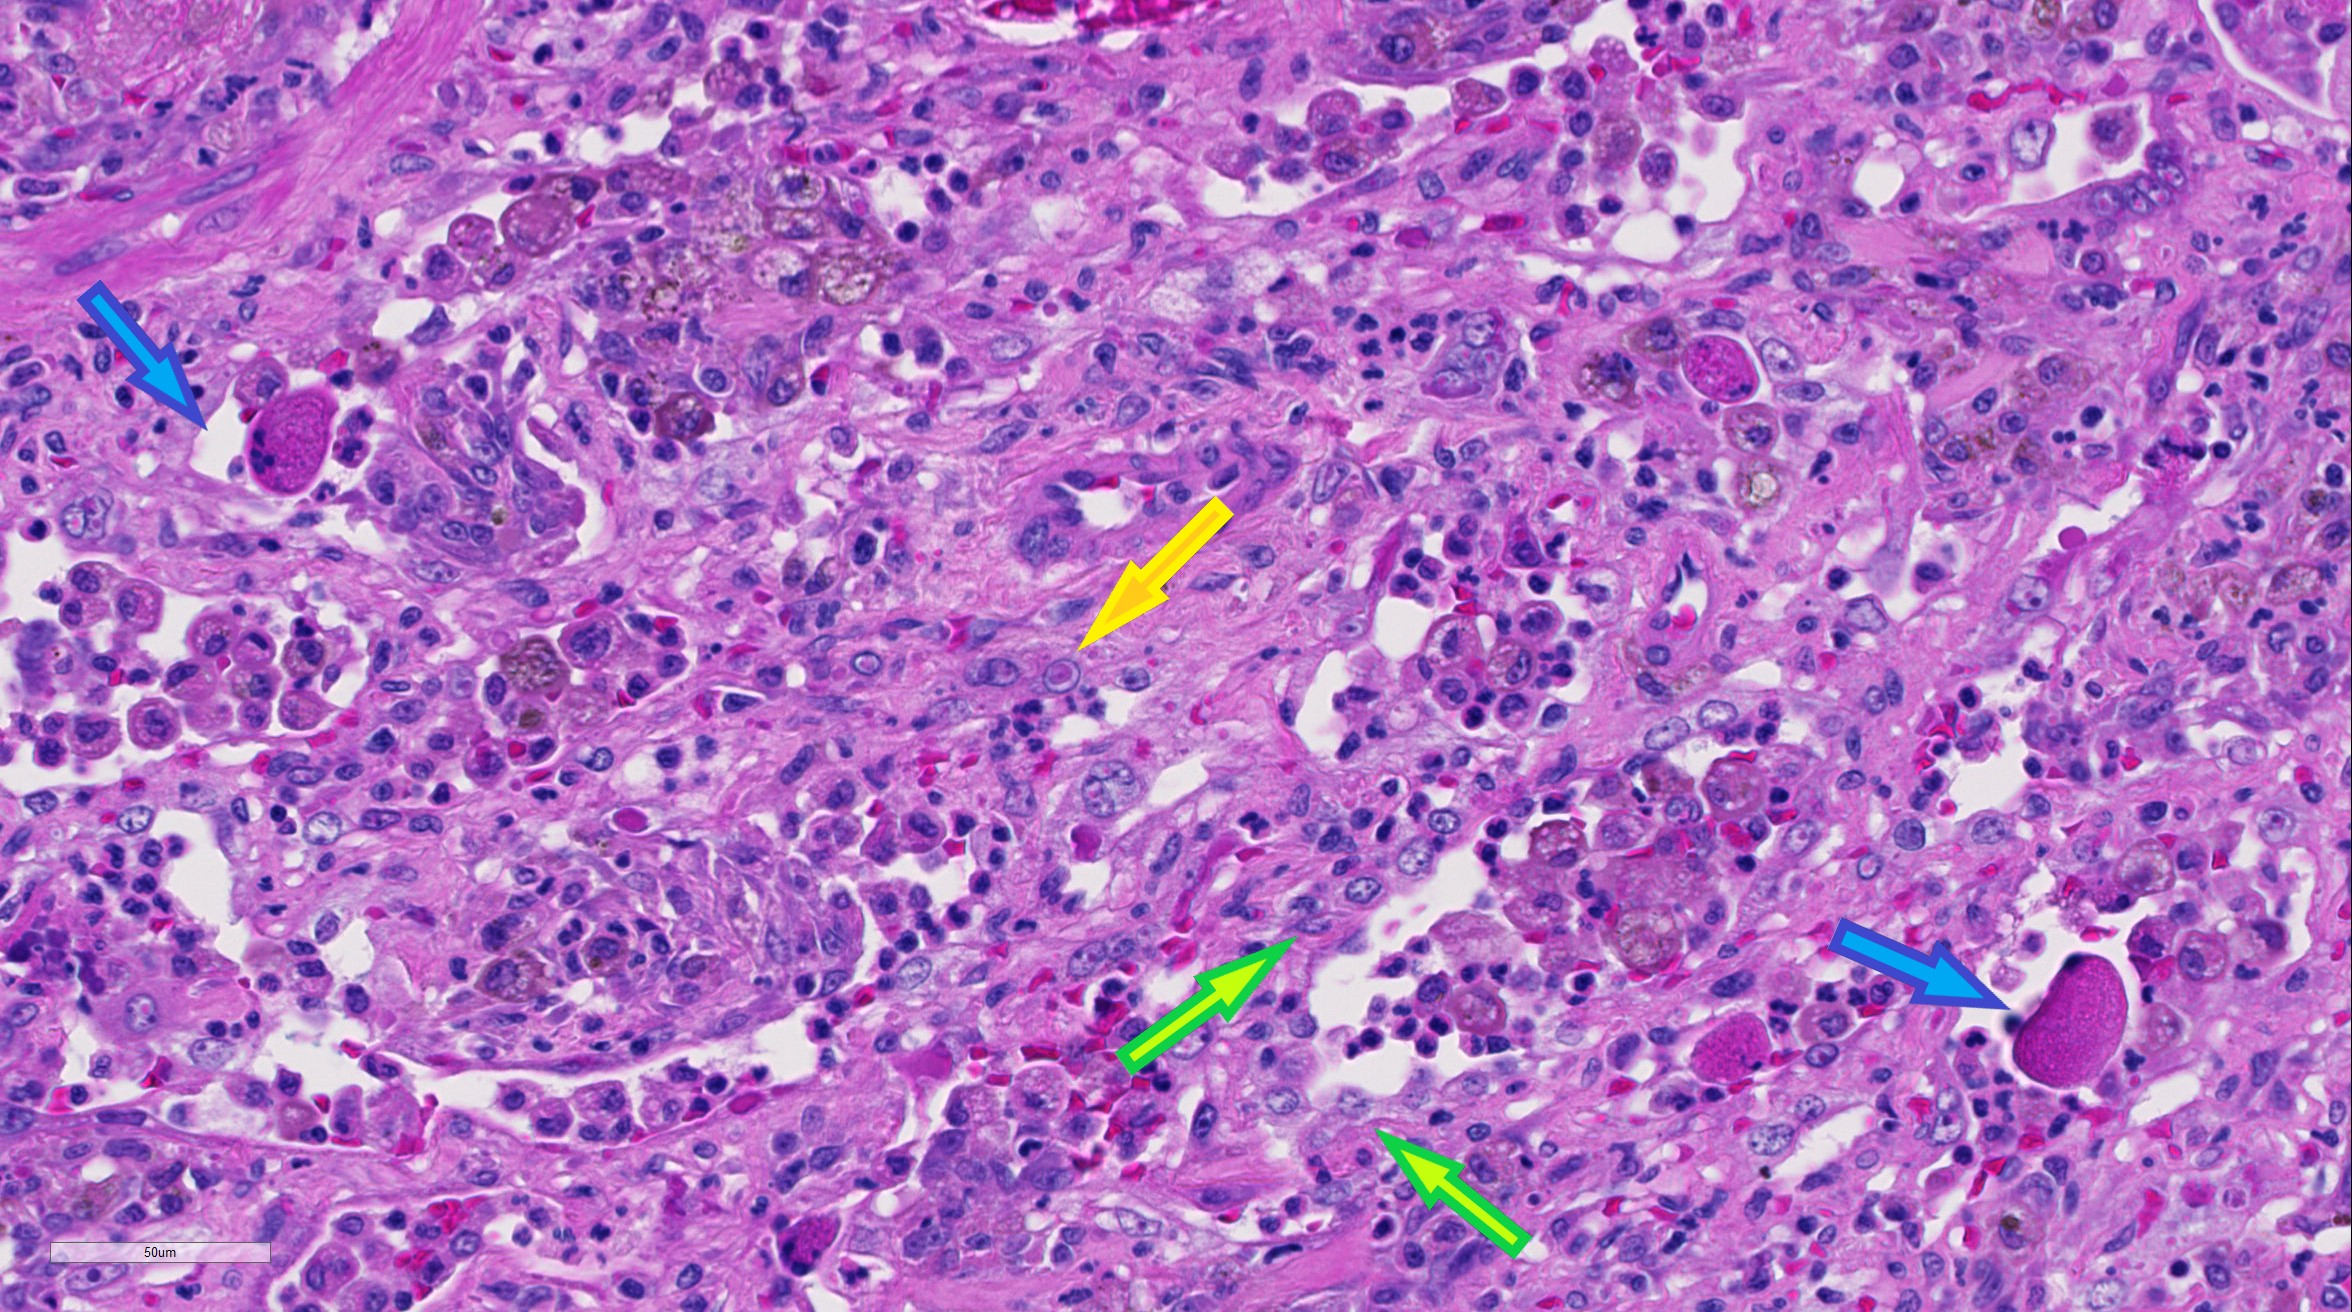

| 40X   |   Hematoxylin and Eosin | ||||

Lung: Alveolar type II pneumocyte hyperplasia (green arrows) and pneumocytes are often multi-nucleated with up to eight nuclei (viral syncytia); syncytial cells are often hypereosinophilic with karryorhectic nuclei (necrosis) and have been sloughed into alveolar lumina(blue arrows); pneumocytes (and/or macrophages) multifocally contain 4um eosinophilic intracytoplasmic and intranuclear inclusion bodies (yellow arrow).